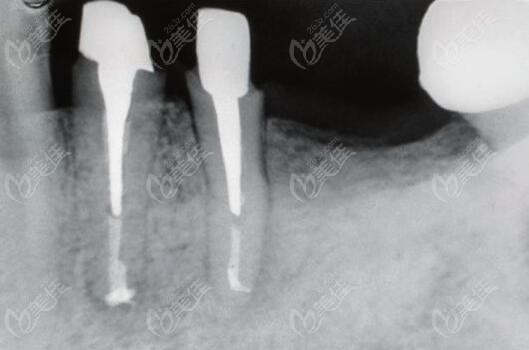

(蛀牙殘根做樁核修復(fù)后的全景片)

如果蛀牙已經(jīng)只剩根了,還可以做樁核冠修復(fù),前提得牙根是穩(wěn)固的。

需要先做根管治療,也就是俗稱的“殺神經(jīng)”,然后在牙根內(nèi)打樁做冠,不過,若牙根已經(jīng)陷入牙齦,非常短小,那可能就做不了樁核冠修復(fù)了,只能是拔掉做種植牙修復(fù)。